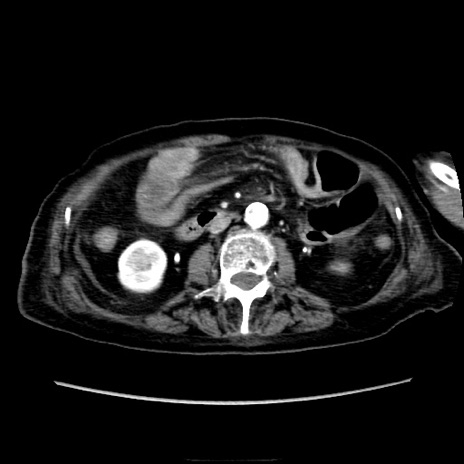

症例40(横断像)

【症例】90歳代女性

【主訴】腹痛・嘔吐

【現病歴】 食欲低下、嘔吐があり昨日他院受診。肺炎と診断され入院となる。入院後より腹部全体に圧痛あり。胃管留置され経過みていたが、症状持続するため、

当院転院となる。

【既往歴】胸椎圧迫骨折、胆石症

【身体所見】腹部:中央に激痛あり、圧痛あり、反跳痛不明

【データ】WBC 17100、CRP 18.82

他院CT

横断像